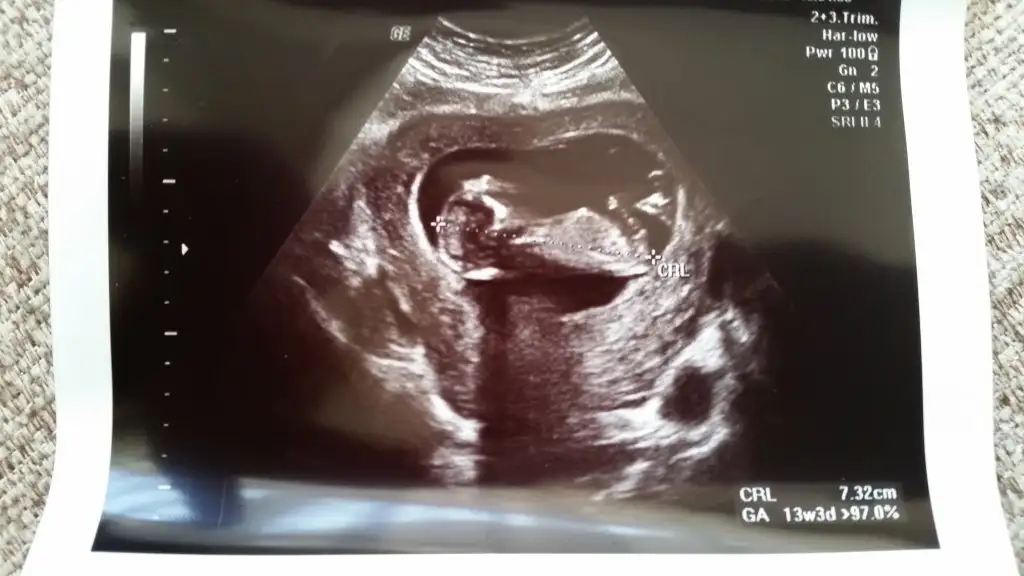

kızlar merhablar şimdi kontrolden geliyorum nolur bi bakın :))) sizce cinsiyetimiz ne ? 12. haftayı doldurduk bugün